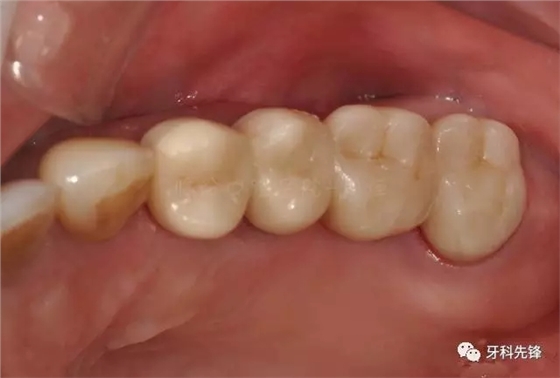

圖2 術(shù)前側(cè)位咬頜照